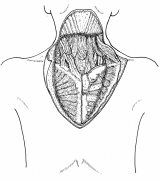

器械吻合器を用いた、咽頭部食道癌摘出後再建法

首の解剖の本と首っ引きで描きました。